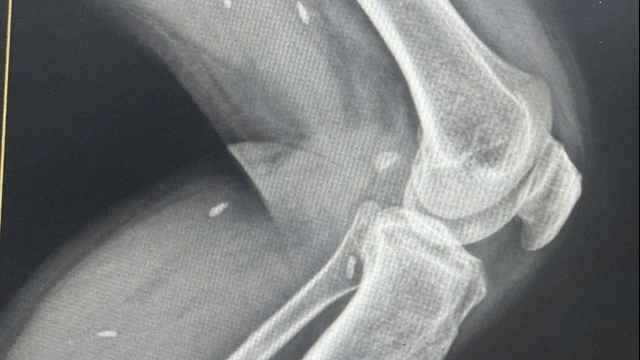

| Y bác sĩ BVDC2.4 khám chữa bệnh cho người dân Nam Sudan |

| Các y bác sĩ BVDC2.4 luôn để lại những ấn tượng tốt đẹp đối với bạn bè quốc tế. |